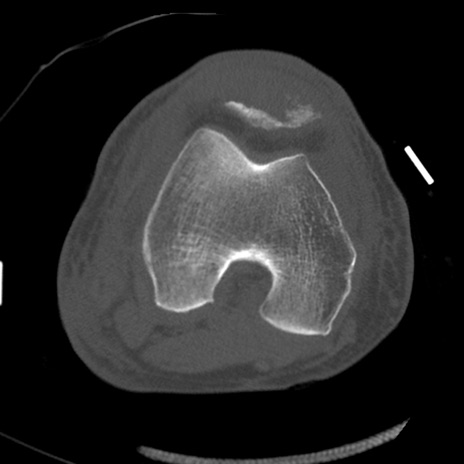

症例28 右膝関節CT(横断像)

右膝関節CT

冠状断像

矢状断像